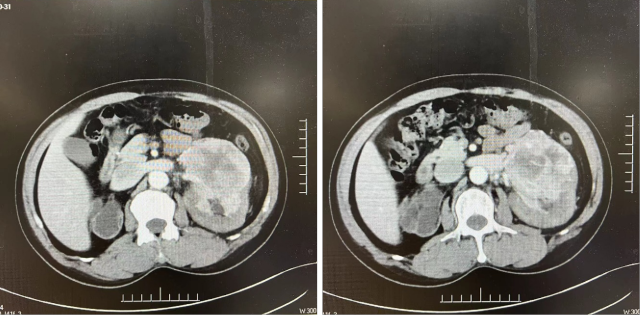

CT(2022.7):1. 右肺转移瘤切除术后改变;2. 左肾上腺结节,转移?3. 左肾多发结节,转移瘤?4. 腹膜后淋巴结肿大,转移可能;5. 左肾多发小囊肿。

PETCT(2022.10):1. 左侧肾上腺结节灶,糖代谢增高,转移瘤可能性大;2. 左肾多发结节状突起,糖代谢增高,考虑转移瘤,需结合增强 CT 综合判断;3. 右下肺切除术后,术区未见复发;4. 右侧胸壁局部增厚、糖代谢增高,术后改变?建议追踪。

靶免联合治疗 1 年后复查

CT(2023.7.17):1. 左肾上腺结节、左肾结节及肿块较前明显增大:转移?左肾 CA 并左肾内、肾上腺转移?2. 腹膜后淋巴结较前增大,转移可能;3. 余况基本同前。

2023.7 开始予以伏罗尼布单靶治疗

CT(2023.12.6):1. 左肾上腺结节较前稍缩小、左肾结节及肿块较前稍缩小;2. 腹膜后淋巴结转移灶同前;3. 余况基本同前。